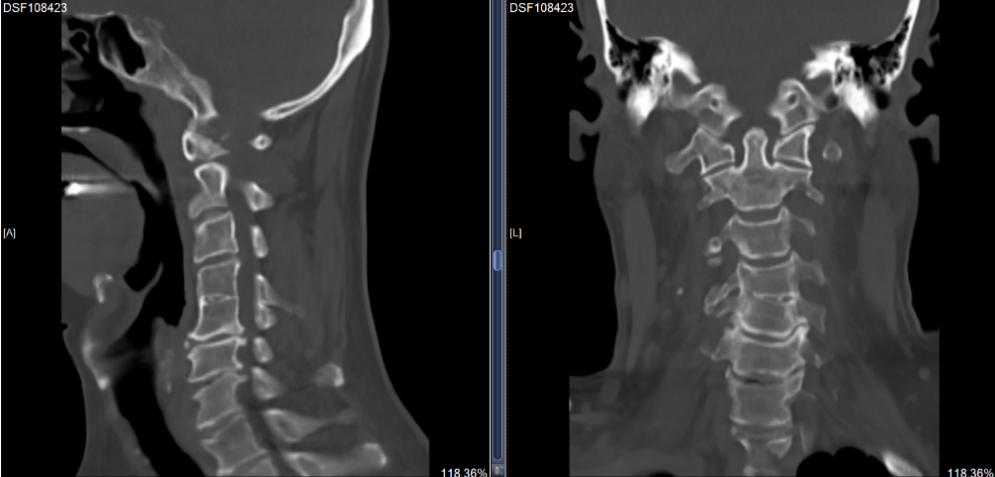

Hester辗转多家医院寻求帮助,其中包括上海著名的三甲医院,都建议手术治疗,他因为担心疗效而犹豫不决。病情的不断加重又使他心急如焚。今年3月初,通过其他专业人士推荐,他前来我院骨科姜为民主任的高级专家门诊就诊。姜主任在仔细询问了他的病史、阅读了他的影像学资料并进行了全面的体格检查后,告诉他共有3个方面的问题:1.颈椎的第四(C4)和第五节椎体(C5)先天发育异常,分节不全;2.C5-6椎间隙倾斜,颈椎侧凸畸形同时伴严重的骨质增生和椎间盘退变。3.磁共振检查显示在C5/6和C6/7水平脊髓严重受压伴脊髓信号明显改变,说明神经损伤已相当严重,尽快手术治疗是唯一的选择。他觉得姜主任对病情的判断与建议与他德国的医生完全一致。“It is a good decision to receive the treatment in the professional hospital which gives me a good feeling at the first sight.”(这是一个正确的决定,我第一眼看到这家医院,就觉得非常的专业)。 在Hester后来的感谢信中写道:Also, the talk with Dr. JiangWeimin and his assistant Dr. Zhao gave me very good feelings. They spent enough time explaining to me with understandable words. It was the professionality of these doctors and the public hospital itself that convinced me to do the next treatment.(姜为民主任和他的助手赵博士与我的交谈非常融洽,他们用通俗易懂的语言耐心地向我解释病情,独墅湖医院是公立医院,专家们所展现出的专业性让我心悦诚服,因此我决定就在这儿接受进一步的治疗)。

患者C4和C5椎体发育异常

C5/6、C6/7椎间盘突出明显,椎管狭窄,脊髓受压严重